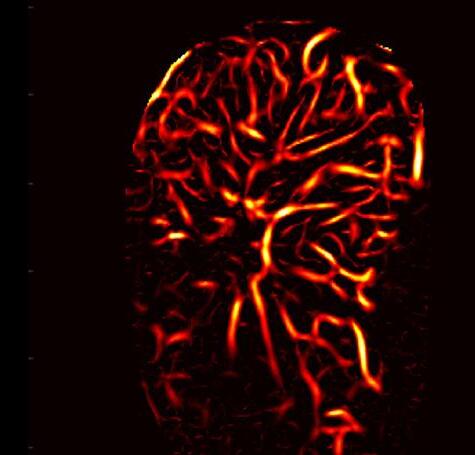

Known as high-definition microvasculature imaging (HDMI), the new technique noninvasively captures images of minute vessels within tumors and automatically categorizes the masses .

ach year, over 40,000 new thyroid cancer cases are reported. While 60-80% of patients with thyroid tumors undergo biopsies, the financial and potential physical toll of these procedures may be unnecessary for those with benign tumors. It is presently challenging for medical practitioners to accurately gauge the severity of a tumor, with different doctors having divergent opinions on a tumor’s threat level.

Standard ultrasound methods, which generate images of tissues and organs based on the sound waves they reflect, are efficient at identifying thyroid tumors. However, the technology can struggle to distinguish the minute sounds emitted from small blood vessels, or microvasculature, from those of the surrounding tissue, despite microvasculature providing vital clues about a mass’s cancerous nature. Although the introduction of contrast agents (chemicals easily visualized and commonly used in medical imaging procedures) allows ultrasound to display detailed images of tumor microvasculature, these substances need to be injected into patients and sometimes cause adverse side effects. While more recent ultrasound techniques can offer clearer nodule images, the ultimate evaluation still relies on the physicians’ subjective judgment.

Researchers at the Mayo Clinic College of Medicine and Science (Rochester, MN, USA; www.mayoclinic.org) have demonstrated that a pioneering cancer diagnostic method, which combines advanced ultrasound techniques with artificial intelligence (AI), can effectively diagnose thyroid cancer. This method — referred to as high-definition microvascu lature imaging, or HDMI — noninvasively captures images of the minute vessels within tumors and, based on vessel characteristics, automatically categorizes the masses. The researchers believe that HDMI could poten tially resolve the long-standing diagnostic challenge of assessing thyroid tumors in a clinical setting.

The researchers developed HDMI in an effort to develop an afford able, noninvasive imaging solution for evaluating thyroid tumors that could deliver quantifiable results and minimize errors. This system uses machine learning, a subset of AI, to assess high-resolution images of tumor microvasculature. The technique has already shown potential in accurately assessing breast tumors. In a recent study published in the journal Cancers, the team tested HDMI on thyroid tumors in 92 patients. They captured images of the tumors using HDMI and analyzed a dozen features related to the size and shape of the microvasculature in the images, including their density and branching points. All patients in the study, in consultation with their physicians, chose to have their tumors biopsied to confirm their malignancy status. Those with tumors deemed cancerous underwent surgery for the removal of the mass.

The researchers provided their machine learning algorithms with 70% of their imaging data from the patient tumors, along with the malignancy status, to teach algorithms how to interpret various features. Through a process of trial and error, the algorithms constructed predictive models, which were then used to determine the status of tumors imaged in the remaining 30% of the data. HDMI’s classifications were accurate 89% of the time, based on the clinical assessments of the biopsies and surgeries. These results suggest that HDMI could be a more reliable diagnostic method than traditional techniques and could spare numerous patients from unnecessary surgeries in the future. The researchers are now refining the method to enhance its accuracy even further. They plan to investigate its performance in diagnosing other types of cancer and whether it can assist in monitoring the effectiveness of chemotherapy on cancerous growths.

“Because HDMI allows you to objectively differentiate benign nodules from malignant ones, it could greatly improve diagnostic accuracy and reduce the number of unnecessary surgeries being done now,” said study author Azra Alizad, M.D., a professor of radiology and biomedical engineering at Mayo Clinic.

Image: A combination of advanced ultrasound and AI could upgrade cancer diagnostics (Photo courtesy of Mayo Clinic)